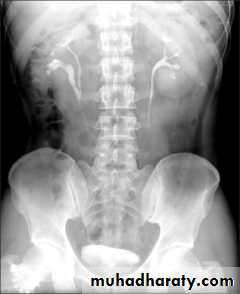

35- Stone without hydronephrosis (left) and stone with hydronephrosis (right)